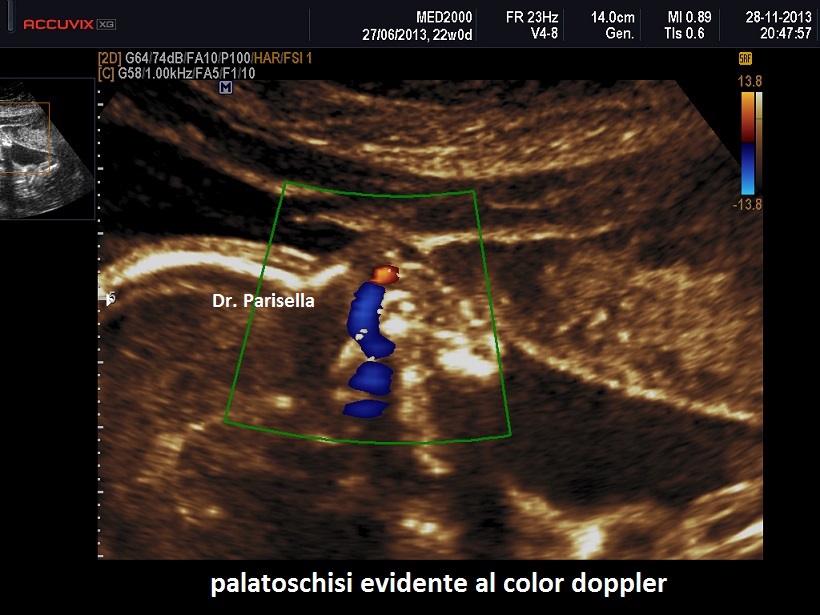

Le lesioni caratteristiche a carico del SNC sono rappresentate  da idrocefalo grave, con ventricoli aperti nello spazio subaracnoideo, ipoplasia cerebrale, anomalie della linea mediana e del setto pellucido (agenesia del corpo calloso); possono essere presenti encefalocele occipitale, una caratteristica conformazione del forame magno “key-hole shaped”, mandibola piccola e naso malformato, labio-palatoschisi. Caratteristica è la polidattilia postassiale alle mani e preassiale ai piedi (l'alluce duplice è altamente caratteristico, quasi esclusivo, di questa condizione morbosa). Segnalati anche piede torto e difetti cardiovascolari (difetti del setto atriale; atrio unico). Come ha segnalato lo studio di Salonen e coll. (1981) condotto su 28 neonati di 18 famiglie, l'esito abituale della gravidanza è la nascita di feto morto o morte in epoca neonatale.

La Diagnosi Prenatale si basa su: 1) assenza di movimenti attivi fetali; 2) polidattilia postassiale alle mani; 3) polidattilia preassiale ai piedi;  4) idrocefalia; 5) polidramnios.